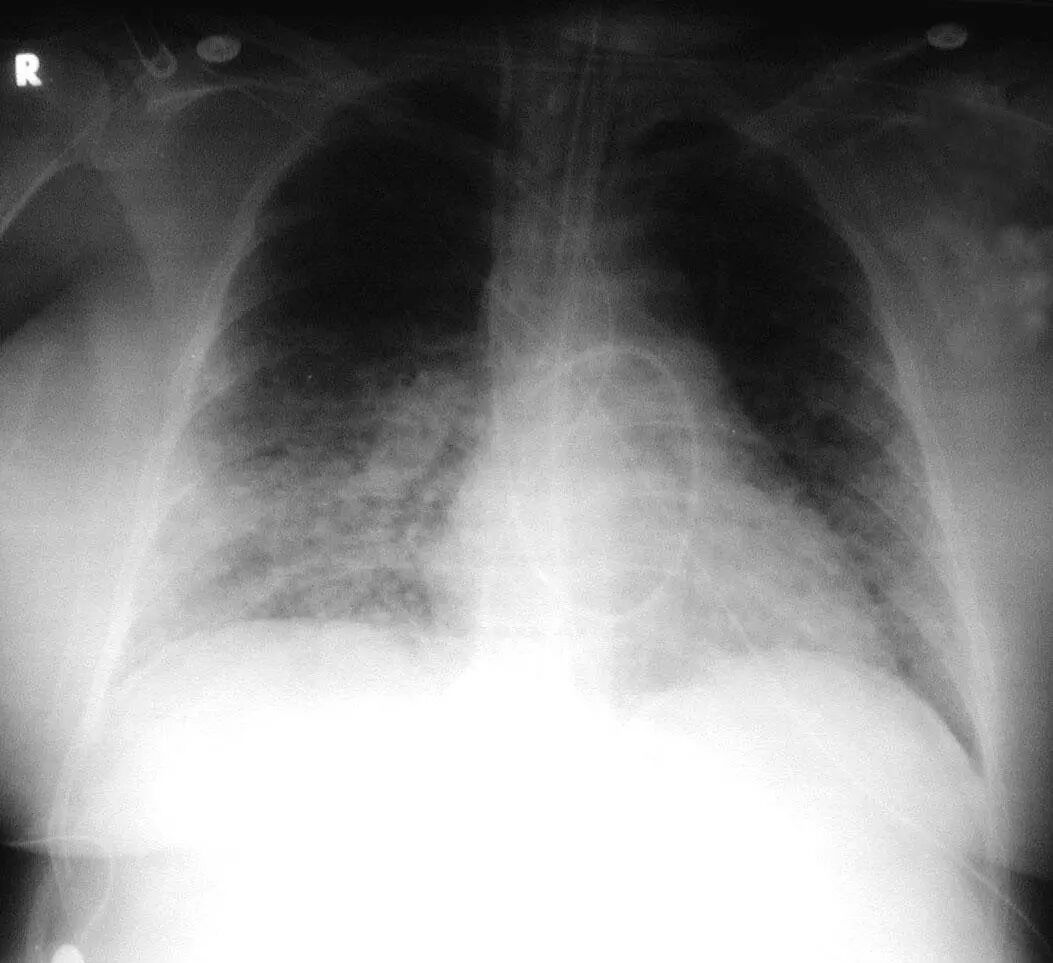

图1.4 53岁的严重军团菌肺炎患者。胸片显示双肺下叶致密实变。